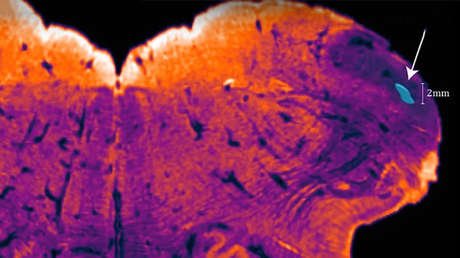

Un equipo de investigadores de la Escuela Médica de Yale, estado de Connecticut, EE.UU., ha conectado los cerebros extraídos de 32 cerdos (adquiridos en instalaciones de procesamiento de alimentos) a un sistema especial que bombea un medicamento rica en nutrientes que imita la sangre, vía las arterias principales. El experimento se llevó a cabo cuatro horas después de la muerte de los animales.

Los resultados del estudio revelaron que el cerebro de los cerdos era sorprendentemente resistente a la falta de oxígeno. Al conectarse a sus 'cuerpos artificiales', los cerebros volvieron a funcionar a un nivel básico.

Sus vasos sanguíneos empezaron a bombear el medicamento y, poco después, también se restableció la función de los capilares. A lo largo de las seis horas del experimento (periodo de descomposición de un cerebro aislado), el número de células moribundas se redujo drásticamente.

Sin embargo, durante el experimento los encefalogramas cerebrales eran completamente planos. En otras palabras, los cerebros examinados no podían pensar ni sentir nada, ni mostraron ningún signo de otras formas de actividad nerviosa superior. En este sentido, conforme a los estándares médicos, no pueden considerarse realmente vivos, señalan los especialistas.